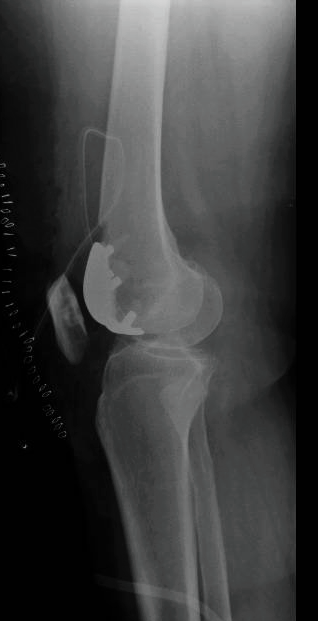

La prótesis total de rodilla es la cirugía más frecuentemente realizada para tratar la artrosis de rodilla. En una intervención con una historia de casi 50 años y es de las cirugías más exitosas que existen afortunadamente. Se realiza la sustitución del hueso desgastado mediante fijación de dos o tres implantes artificiales entre el fémur, la tibia y el fémur. Tras una minuciosa discusión con el paciente, el cirujano decidirá el tipo del implante a usar dependiendo de su edad, forma de los huesos (anatomía), nivel de actividad y calidad de hueso entre otros factores. Un minucioso estudio de planificación clínico antes de la cirugía permitirá la elección de los implantes que se requiere para adaptarlos y corregir la deformidad de la rodilla y de la pierna. Esa planificación hecha más habitualmente con radiografías permite elegir los implantes adecuados y prever los escenarios que pueden encontrarse en el quirófano – un paso imprescindible para el éxito de la cirugía. Los cirujanos de rodilla deben dominar un amplio repertorio de implantes para adecuarlo a cada situación. Los tres tipos de prótesis de rodilla son: la total, la unicompartimental y la femoropatelar.

El que se usa de manera normal con excelentes resultados a largo plazo es la prótesis total de rodilla. Las prótesis de rodilla cementada consisten de tres implantes fijados al hueso con cemento: una arriba en el fémur (muy liso y hecho frecuentemente de Cobalto Cromo), una base implantada dentro de la parte proximal de la tibia tras resecar su superficie (de titanio) y un botón de plástico en la patela. Entre el fémur y la tibia se inserta un plástico de polietileno con propiedades especiales que limita el desgaste o rotura.

La prótesis total de rodilla no-cementada es una opción usada en ocasiones para la fijación del implante en el fémur y la tibia en pacientes jóvenes con muy buena calidad ósea. La superficie de estos implantes son rugosas y diseñada para adherirse (integrarse biológicamente) al hueso. La fijación de los implantes inicialmente depende de una impactación mecánica muy precisa pero el buen resultado a largo plazo está basado en la osteointegración biológico entre el hueso y el implante. Se indica su uso por las características de forma y calidad del hueso y no han presentado grandes diferencias en los resultados funcionales o de supervivencia entre los dos sistemas (cementado o no-cementado). La ventaja de la protesis no cementada es que parece ser conservar más el hueso.